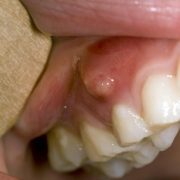

- آبسه جینجیوال (Gingival abscess): این آبسه روی لثه است.

- آبسه پری اپیکال (Periapical abscess): این آبسه در نوک ریشه دندان است.

- آبسه پریودنتال (Periodontal abscess): این آبسه داخل لثه و در کنار ریشه دندان است. همچنین ممکن است به بافت و استخوان اطراف آن گسترش یابد.